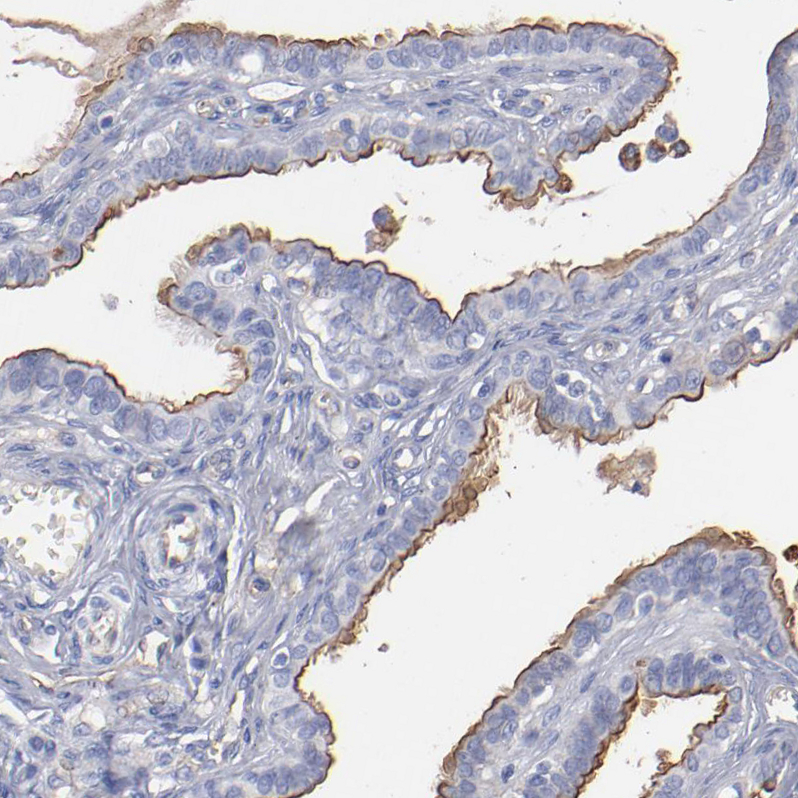

Immunohistochemical staining of human Ovarian cancer shows strong positivity in tumor cells.